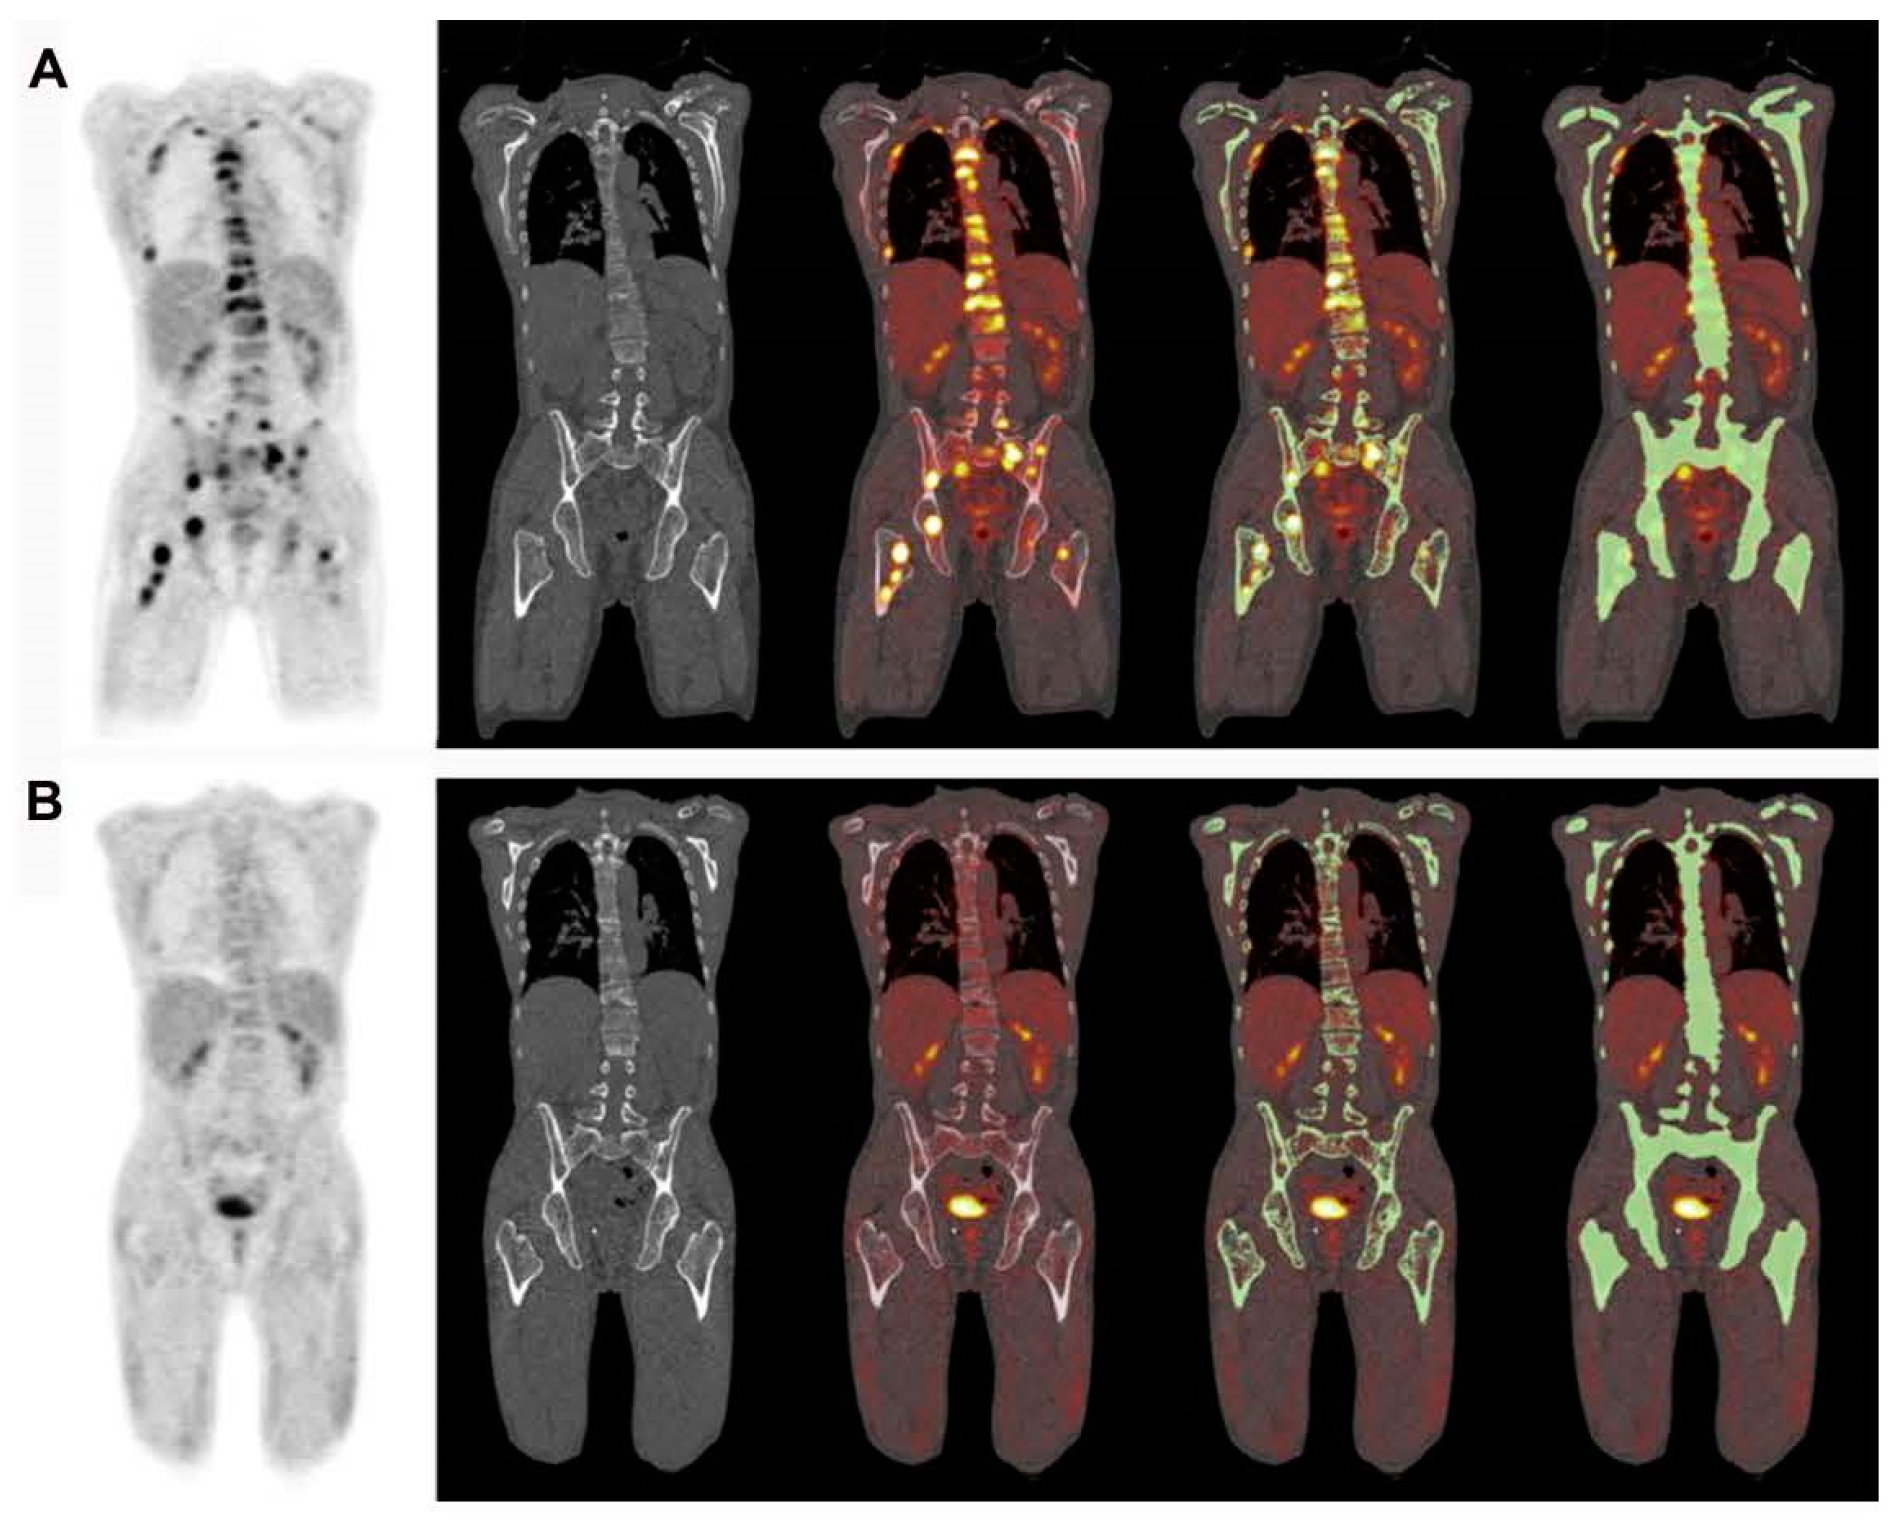

Certain research teams have recently proposed using CT-based segmentation to analyze the uptake of radiotracers in the bone marrow and the overall bone structure of myeloma patients as an alternative to concentrating solely on specific osteolytic lesions [23] (Figure 10 and Figure 11). These approaches have demonstrated a high level of reproducibility [23] (Table 1). However, the clinical significance of these methods still needs to be investigated further [23]. This method has recently been used by the Penn–Odense group to assess the uptake of [18F]FDG in the context of dual-time-point imaging (Figure 12) [35]. Pre-treatment [18F]FDG PET/CT scans from 36 patients with MM were collected [35]. These scans were conducted at 1 and 3 h after the injection of the tracer. A segmentation and quantification of whole-bone marrow (WBM) [18F]FDG uptake was performed using a threshold algorithm utilizing Hounsfield units obtained from CT data [35]. The patients were split into two treatment groups: one received non-HDT, and the other received HDT with ASCT. The international response criteria were utilized to assess the treatment outcomes for each multiple myeloma patient. In the group that underwent HDT, there was a notable increase in WBM [18F]FDG uptake among patients who responded poorly to treatment (Figure 12) [35]. The median value escalated from 1.31 (with an interquartile range, IQR, of 1.13–1.64) after one hour to 1.85 (IQR: 1.45–2.10) at the three-hour mark, illustrating this increase [35]. The calculated median percentage alteration ranged from 6.10% to 50.73% (IQR: 23.47–46.4; p = 0.003). In contrast, there was no apparent change in uptake for patients exhibiting a complete response (p = 0.24) (Figure 12). A similar pattern was observed in the non-HDT group [35].

Figure 10.

This figure demonstrates the potential role of global disease assessment by PET in MM. It shows changes in [18F]FDG uptake in MM lesions before (A) and after treatment (B). High diffuse [18F]FDG uptake is visible across the entire spine before treatment (A), whereas a substantial reduction in [18F]FDG uptake can be visually observed after treatment (B). Segmentation of the entire skeleton followed by a closing algorithm allows for a global disease assessment (C,D). The pre-treatment global average SUVmean (C) was 3.1 and decreased to 1.8 after the completion of the treatment (D). The image was sourced from PMID: 31084774 (Figure 4), and permission was granted for its use.

Figure 11.

This presents the whole-body [18F]FDG PET and combined [18F]FDG PET-CT images of a 60-year-old man diagnosed with multiple myeloma. The entire skeleton was segmented by employing an iterative threshold algorithm based on Hounsfield units, followed by a smoothing and closing procedure. This method yields the global SUVmean (GSUVmean), which represents the total bone marrow involvement in patients with multiple myeloma. (A) Prior to treatment commencement, the GSUVmean was 2.02. However, (B) upon completing the treatment, the GSUVmean significantly decreased to 1.10. The image was sourced from PMID: 30420215 (Figure 6), and permission was granted for its use.

Figure 12.

The upper row of images includes a PET scan (A), a merged PET/CT scan (B), and a combined PET/CT scan with a region of interest (ROI) applied before the use of the morphological closing algorithm (C) in a patient with multiple myeloma (MM). In the bottom row, the left-hand side images display PET scans of an MM patient classified in the poor response to treatment group, captured at 1 h (D) and 3 h (E). In this patient, the overall bone marrow [18F]FDG uptake escalated from 0.89 (D) to 2.31 (E), reflecting a percentage change of 158.15%. On the right-hand side of the bottom row, the images present PET scans of an MM patient from the complete response group, taken at 1 h (F) and 3 h (G). In this patient, there was a slight reduction in the overall bone marrow [18F]FDG uptake, dropping from 0.83 (F) to 0.82 (G), with a percentage change of −0.79%. Note that the second decimal number is rounded up. PMID: 33224622, PMCID: PMC7675111, Free Access.